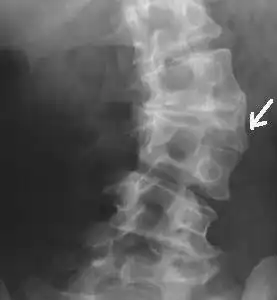

年轻人的发育不良性腰椎滑脱峡部裂应当引起重视

腰椎峡部裂1例